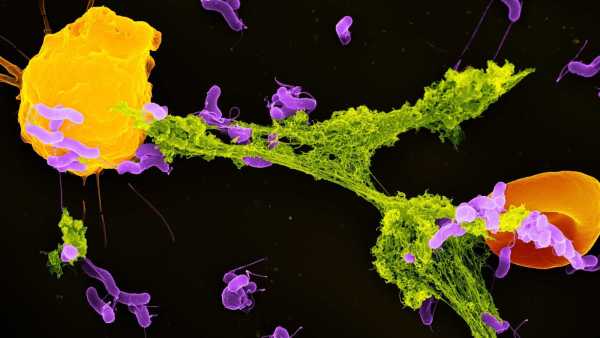

Ілюстрація, що показує пошкодження нейронів, яке може завдати розсіяний склероз. (Зображення: JUAN GAERTNER/SCIENCE PHOTO LIBRARY via Getty Images)

Розсіяний склероз (РС) – це аутоімунне захворювання, яке викликає запалення в головному та спинному мозку. Це запалення пошкоджує мієлінові оболонки – ізоляцію, яка огортає довгі «дроти» нервових клітин – і призводить до таких симптомів, як біль, втома, оніміння або слабкість, а також проблеми із зором або рухом.

Відомо, що у людей з розсіяним склерозом (РС) високий рівень імунних клітин, які називаються цитотоксичними Т-клітинами, що зазвичай допомагають знищувати ракові та інфіковані мікробами клітини. Однак при РС ці клітини накопичуються в ділянках з видимим пошкодженням мієліну, але роль, яку ці клітини відіграють у цьому захворюванні, досі залишалася значною мірою загадкою.